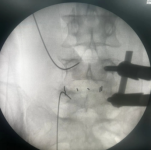

3.微创PKP技术:老年压缩性骨折球囊扩张椎体成形术

经皮球囊扩张椎体后凸成形术是性爱视频

很早就开展的一项微创技术,已经有20多年,每年手术约200例,尤其适用于老年骨质疏松引起的胸腰椎骨折;椎体转移性肿瘤(溶骨性破坏);引起疼痛症状的椎体血管瘤、多发性骨髓瘤、Kummell 症。局部麻醉,创伤小恢复快,第二天可以下床活动,迄今为止最高手术患者92岁高龄。